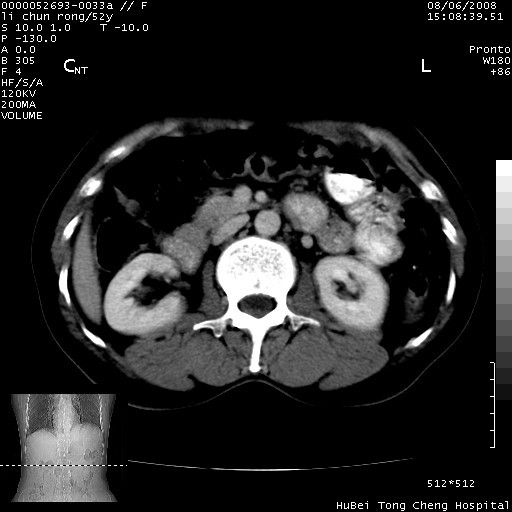

以下是引用云翔在2008-8-7 6:20:00的发言:[br]胰尾部囊性病变,考虑假囊肿,结合实验室检查疾病史

以下是引用zjzjr在2008-8-7 8:38:00的发言:[br]支持胰腺炎伴假囊肿形成,左肾小囊肿.少量腹水.

以下是引用随光逐影在2008-8-7 9:12:00的发言:[br]1)考虑胰腺炎伴假性囊肿形成可能性大;胰腺囊腺瘤待排。2)左肾小囊肿。3)少量腹水。